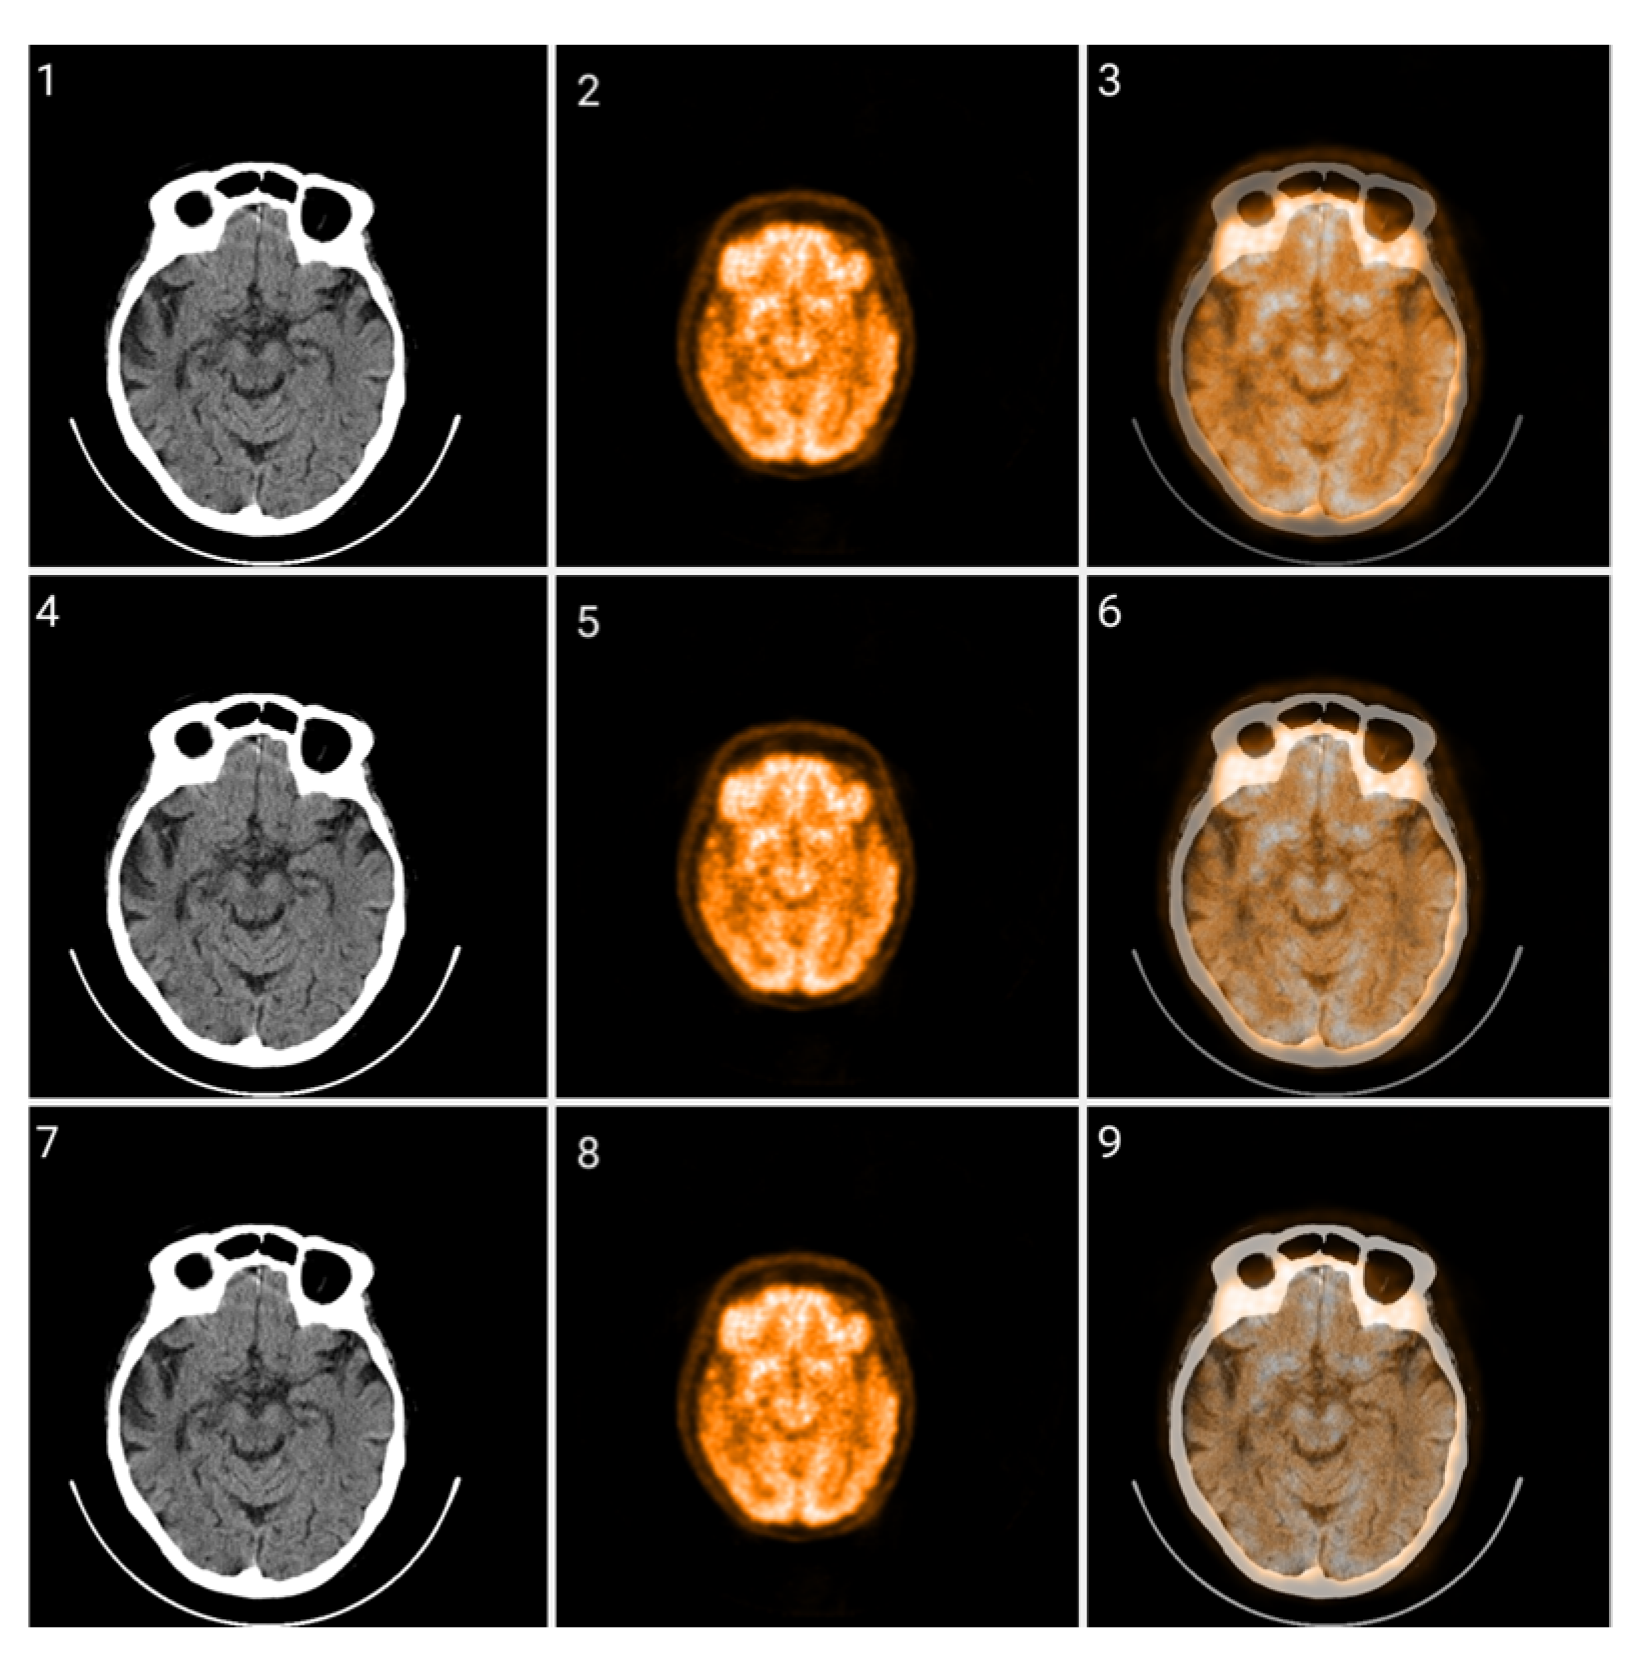

Figure 12.

Fusion of CT and PET images at different ratios. Images 1, 4, and 7 present a standard windowed CT image. Images 2, 5, and 8 present the corresponding PET image after Colormap Folding by 1 fold. Images 3, 6, and 9 present the results of fusing the CT and PET images at different ratios, 35%, 50%, 65% CT with 65%, 50%, 35% PET, respectively.